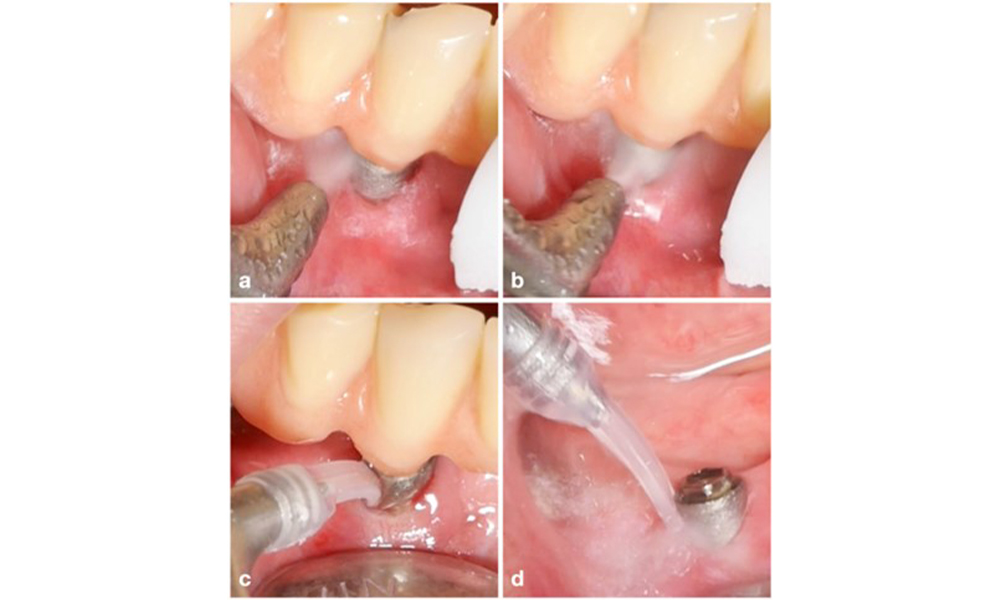

Лечението на периимплантит при импланти, оценени като лечими, се състои от нехирургична фаза, която често е последвана от хирургична интервенция. Нехирургичните процедури са подобни на тези, прилагани за лечение на периимплантатен мукозит. Лабораторните експерименти показват, че устройствата за въздушно полиране със субгингивални накрайници изглежда осигуряват определени предимства по отношение на отстраняването на биофилм в сравнение с ръчните или ултразвукови инструменти (Herrera et al. 2023; Moharrami et al. 2019; Ronay et al. 2017) ( фигура 9).

Случай на пациент с периимплантит. Нехирургичното лечение се извършва с помощта на супрагингивален (a-b) и субгингивален накрайник на апарат за въздушно полиране (c-d). Премахването на надстройката осигурява по-добър достъп до повърхността на импланта (d).

Фигура 9. Случай на пациент с периимплантит. Нехирургичното лечение се извършва с помощта на супрагингивален (a-b) и субгингивален накрайник на апарат за въздушно полиране (c-d). Премахването на надстройката осигурява по-добър достъп до повърхността на импланта (d).